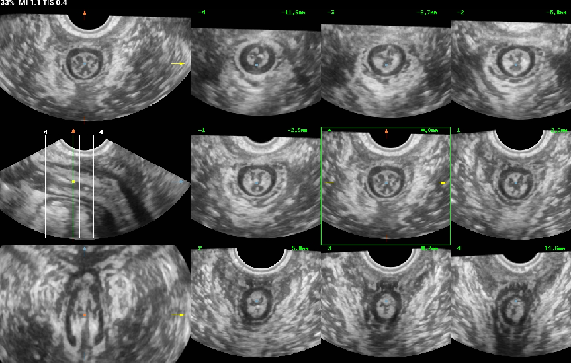

盆底超聲是利用超聲探頭經(jīng)會(huì)陰、陰道或直腸檢查,觀察在靜息、縮肛及Valsalva三種狀態(tài)下的盆腔臟器位置變化,結(jié)合多種成像方法(二維超聲、三維/四維容積超聲、斷層超聲成像)評(píng)估盆腔臟器脫垂程度、肛提肌裂孔大小及肛提肌、肛門內(nèi)外括約肌的完整性,同時(shí)能評(píng)估尿道、陰道及肛門周圍病變,也能用于盆底修復(fù)術(shù)前、術(shù)后及盆底康復(fù)療效的評(píng)估。具有無(wú)輻射、無(wú)創(chuàng)傷、可重復(fù)性好、實(shí)時(shí)動(dòng)態(tài)、價(jià)格低廉等優(yōu)勢(shì),有利于疾病的早期發(fā)現(xiàn)、早期診斷,在臨床癥狀出現(xiàn)前或癥狀較輕時(shí)通過(guò)物理治療來(lái)恢復(fù)盆底支持結(jié)構(gòu)功能,避免或者延緩手術(shù),提高患者生活質(zhì)量。

13.分娩后肛提肌評(píng)估